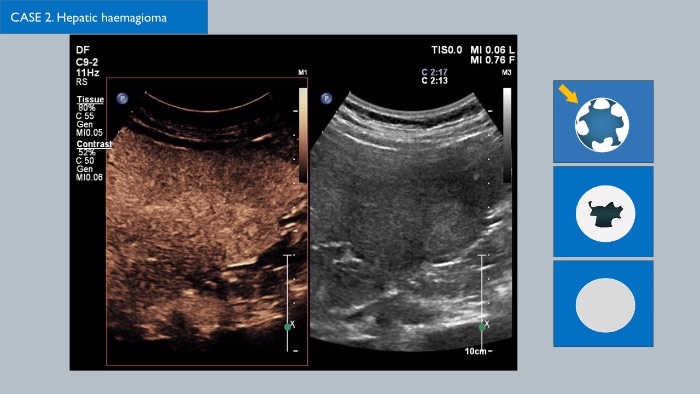

Ultraschall-Kontrastmittel können die Rolle des Ultraschalls verändern: Verstärkungsmuster von Leberläsionen können in Echtzeit untersucht werden, was zu einer schnelleren und fundierteren Diagnose führt.